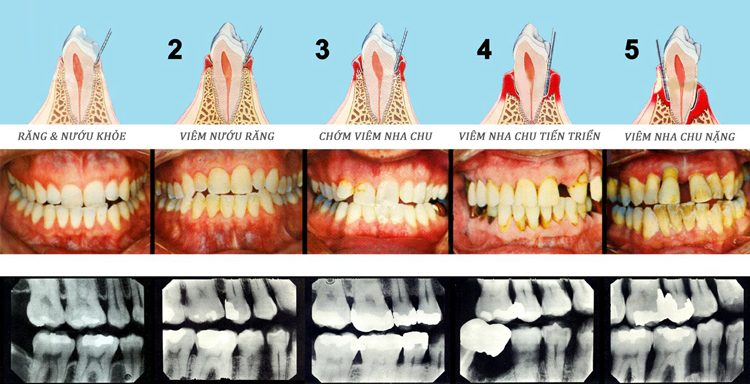

2. Viêm Nướu và Viêm Nha Chu (Gingivitis & Periodontitis)

Bệnh nha chu là nguyên nhân hàng đầu gây mất răng ở người trưởng thành. Khởi đầu là viêm nướu với triệu chứng chảy máu và sưng nướu. Nếu không điều trị, vi khuẩn tấn công sâu hơn vào mô nâng đỡ răng và xương ổ răng, gây viêm nha chu với tình trạng mất xương không thể hồi phục.

Nướu khỏe mạnh không bao giờ chảy máu khi đánh răng đúng cách. Chảy máu nướu là dấu hiệu của viêm nướu (gingivitis) – giai đoạn sớm của bệnh nha chu. Nếu không điều trị, viêm nướu sẽ tiến triển thành viêm nha chu, phá hủy xương ổ răng và cuối cùng dẫn đến mất răng vĩnh viễn.

Nguyên nhân phổ biến nhất là viêm nha chu giai đoạn nặng đã phá hủy xương ổ răng. Nguyên nhân khác có thể là chấn thương, u nang xương hàm hoặc bệnh lý toàn thân như loãng xương. Phát hiện và điều trị sớm có thể giúp giữ lại răng; để quá muộn, nhổ răng sẽ là điều không thể tránh khỏi.